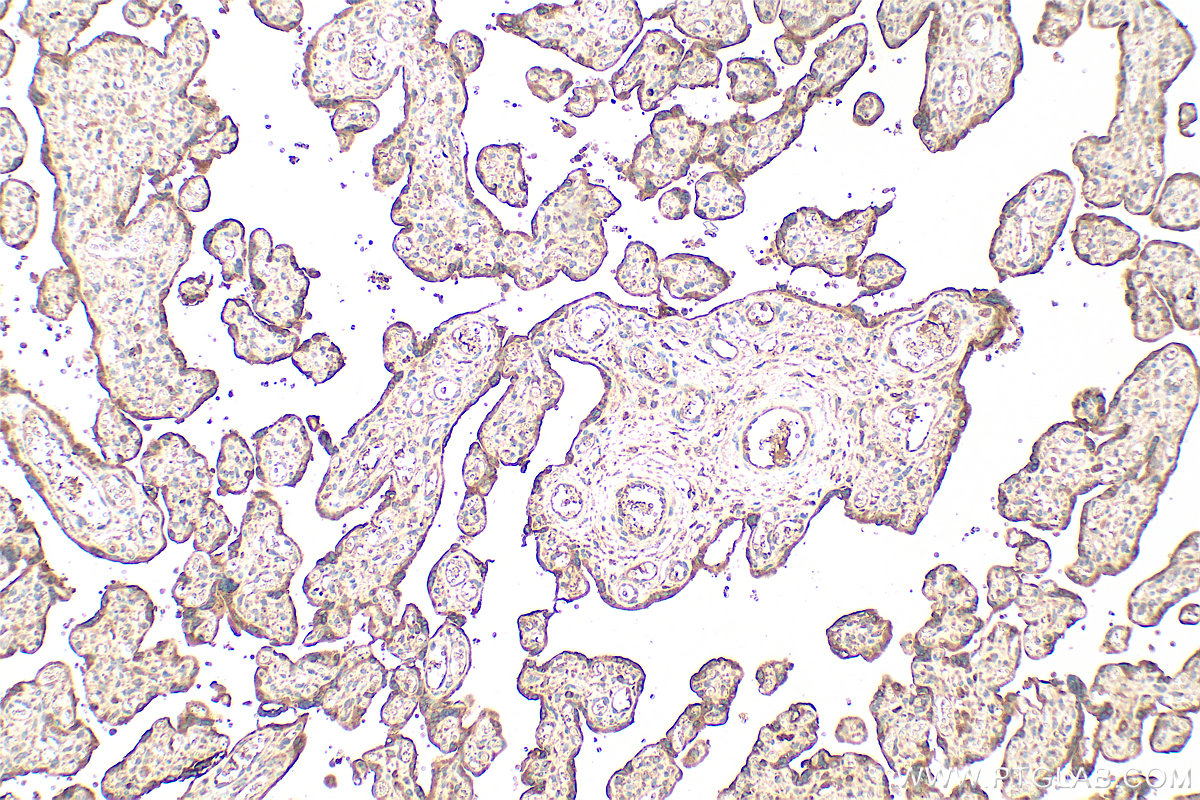

| Positive IHC detected in | human placenta tissue, human lung cancer tissue, human malignant melanoma tissue Note: suggested antigen retrieval with TE buffer pH 9.0; (*) Alternatively, antigen retrieval may be performed with citrate buffer pH 6.0 |

| Immunohistochemistry (IHC) | IHC : 1:200-1:800 |